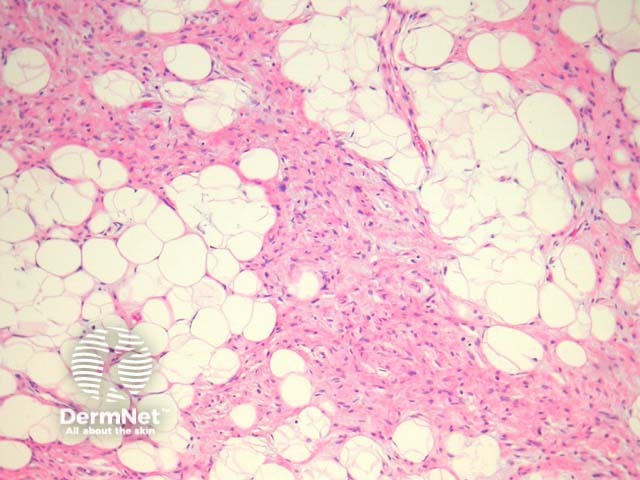

The classic spindle cell lipoma is composed of bland spindled cells intermixed with mature adipose tissue (figure 1). The spindled cells are uniform with narrow bipolar cytoplasmic processes (figure 2). Extensive myxoid change may be evident (figure 3) and there are often numerous mast cells (figure 3, arrows show mast cells). Ropey collagen is frequently seen which has been compared with grated carrot (figure 4, arrow shows classic collagen).

Figure 1